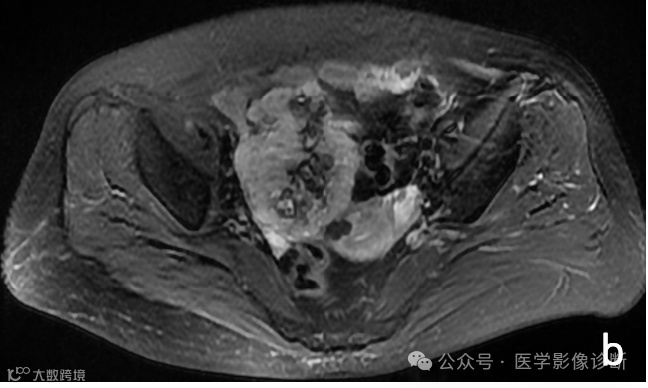

Case 2

患者,男性,81岁,上腹不适半年。

影像学表现

胰腺尾部占位性病变,轴位MRI T1WI (a)、T2WI/FS (b)、T1WI/FS (c)、增强(d)序列均显示病变信号与脾脏相似,但是放射医生诊断为相对常见的胰腺神经内分泌肿瘤,而非罕见的异位脾脏。手术病理证实为胰腺内异位脾脏。